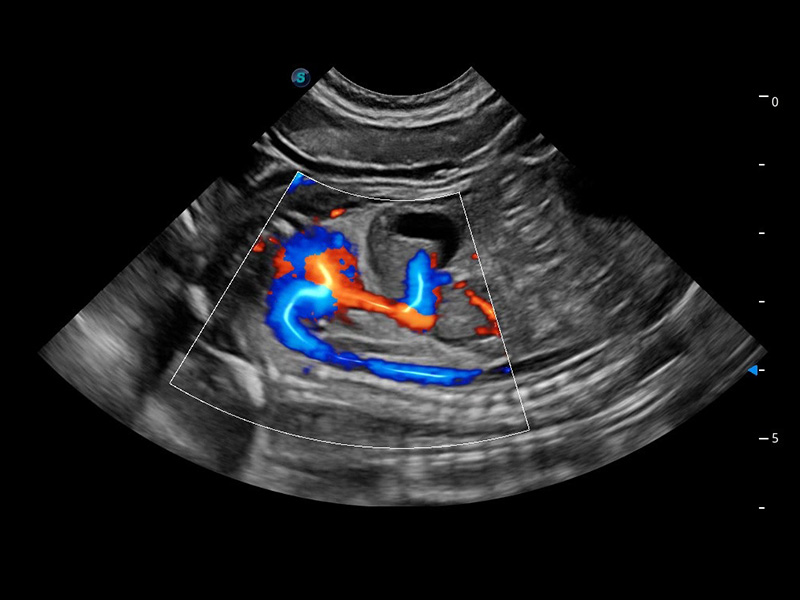

ProPet 60 作为一款高端台式动物超声设备,为动物医生的日常诊断提供了一系列贴合动物临床需求、解决临床实际问题的高级成像功能。凭借全系列高清探头,满足医生对腹部、心脏、生殖、浅表、肌骨等成像的所有需求,切实帮助您提升检查效率,提高诊断信心。

兽用彩色多普勒超声诊断系统

动物是人类最亲密的朋友和最值得信赖的伙伴。milan米兰也一直致力于探索动物专用的超声影像解决方案。 全新推出的ProPet系列,是milan米兰在动物超声影像智能化、专业化、精准化的一次跨越式革新。动物不能用言语来表述自己的不适,通过超声影像,ProPet系列搭建了动物医生与不同物种沟通的“桥梁”,为动物医生注入了“治愈之力”。